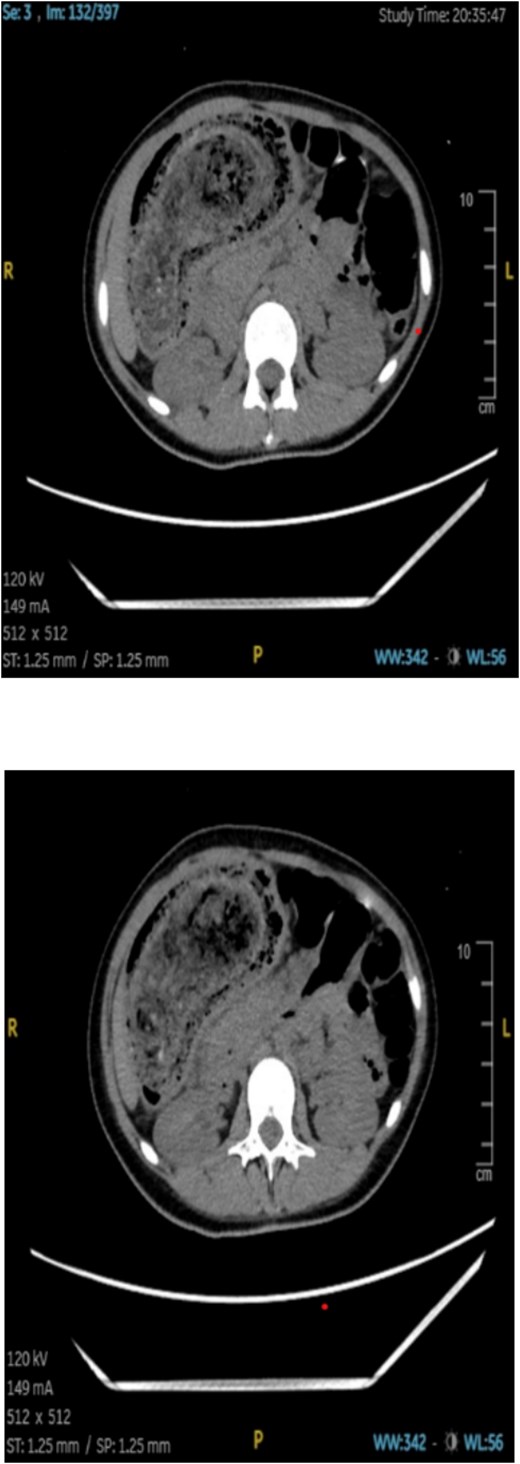

An abdominal CT scan showed a large, intragastric mass with a characteristic mottled appearance and gas entrapment (Figs 1 and 2), consistent with a trichobezoar. The mass extended into the duodenum, confirming the diagnosis of Rapunzel syndrome.

CT imaging played a crucial role in the diagnosis; the characteristic “mottled gas” appearance of the mass helped differentiate the trichobezoar from other gastric masses or tumors. Upper GI endoscopy can also be diagnostic and therapeutic in smaller cases, but large bezoars like the one described typically require surgical removal.